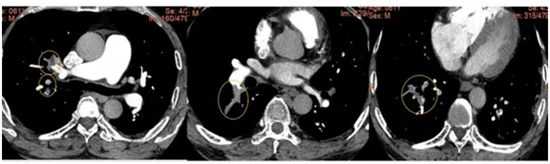

经肺动脉CTA检查,发现刘先生患上了大面积的“肺动脉栓塞”,情况危急,随即被收治入院。下肢静脉彩超进一步显示,其右腿深静脉血栓已蔓延至大腿根部。医疗团队迅速为他施行了“下腔静脉滤器植入术”,术后配合抗凝及溶栓治疗,刘先生的症状很快缓解。

▲ 术前肺动脉CTA,肺动脉主干多发血栓